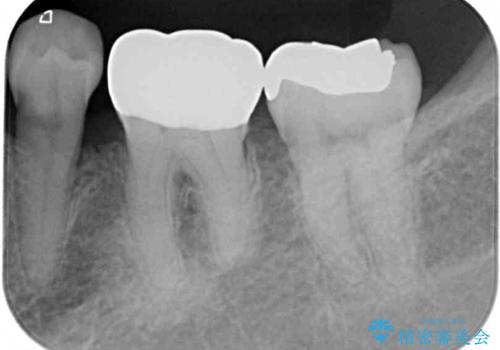

- 奥歯の目立つ銀歯と、神経が失活して変色した前歯を気にして来院された患者様です。

銀歯と歯の間に隙間があり、冷たいものがしみる知覚過敏の症状が認められたため、銀歯を白くするだけでなく、知覚過敏症状の改善も狙って補綴治療を行うこととしました。